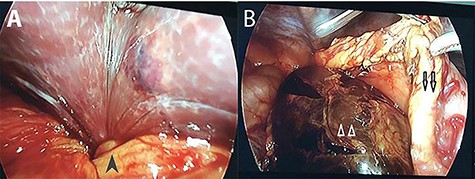

An emergency operation was indicated. Initially, we approached the abdominal cavity with laparoscopy and the gallbladder was not seen in its normal location. Then, the greater omentum was opened and the stomach was retracted superiorly. The gallbladder was found to herniate into the lesser sac through the foramen of Winslow. The infundibulum was twisted and the whole gallbladder was necrotic with darkened color (Fig. 2). We attempted to bring the gallbladder back to the normal position through the foramen of Winslow with laparoscopy but we failed to do so. Therefore, we decided to shift to laparotomy and saw the gallbladder, which was rotated three times counterclockwise, through the foramen of Winslow. The width of the foramen was ~4 cm. Then, the gallbladder was removed and the foramen of Winslow was narrowed with the greater omentum. A suction drain was placed in the hypochondriac region. The patient had an uneventful postoperative course and was discharged on postoperative Day 10. The histopathology was cholecystitis.

Intra-operative photographs: A: the torsion point at the gallbladder infundibulum (black arrow head); B: necrotic gall bladder (white arrow heads) located posterior to the stomach (black arrows).